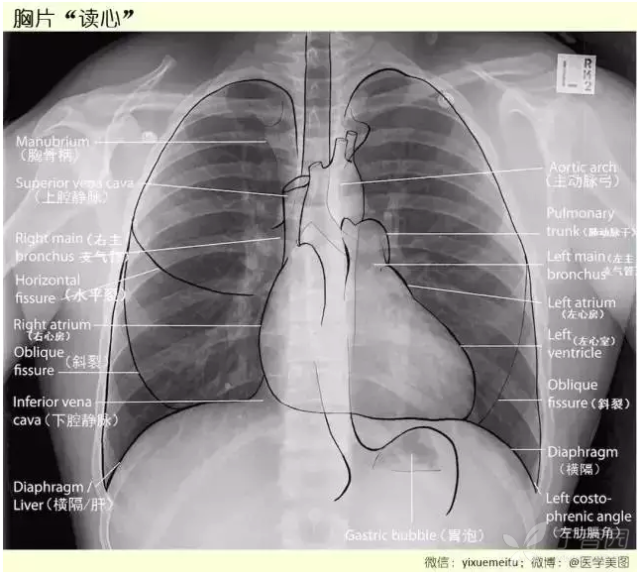

秒懂胸片!